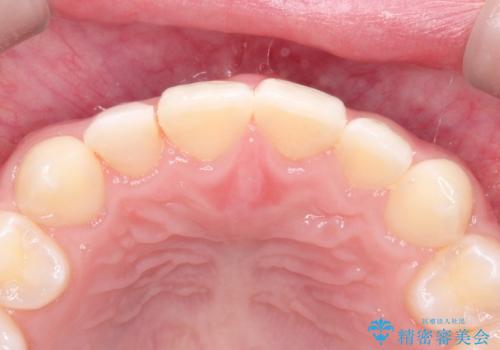

正中の隙間をインビザライン矯正で閉鎖して、右上の2番目の歯にはセラミックを装着する計画としました。

矯正治療とセラミック治療を組み合わせることにより、審美的により良い結果を得ることができました。